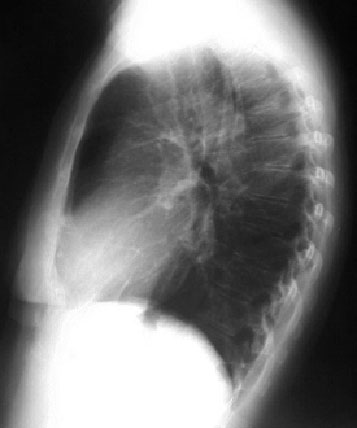

Observa estas dos imágenes que parecen similares. En ambas hay un aumento de densidad en la parte superior del contorno mediastínico derecho. Sin embargo, la de la izquierda se extiende por encima de la sombra de la clavícula, mientras que la de la izquierda acaba a la altura de ésta. En la radiografía posteroanterior de tórax, si una lesión mediastínica sobrepasa el borde superior de la clavícula, debe ser posterior, ya que el mediastino anterior no sobrepasa ese nivel. En el caso de la imagen izquierda hablamos de signo cervicotorácico positivo y en la imagen derecha de signo cervicotorácico negativo.

La imagen de la izquierda se trataba efectivamente de una lesión posterior, concretamente de una metástasis vertebral (flecha roja), mientras que la de la derecha es una elongación de troncos supraaórticos. La flecha blanca señala la arteria subclavia derecha. Esta está en contacto con el pulmón y por tanto puede verse su contorno lateral. Por encima de este plano (a la altura del borde medial de la clavícula) el vaso queda rodeado de la grasa mediastínica y por tanto su contorno desaparece (hace silueta).